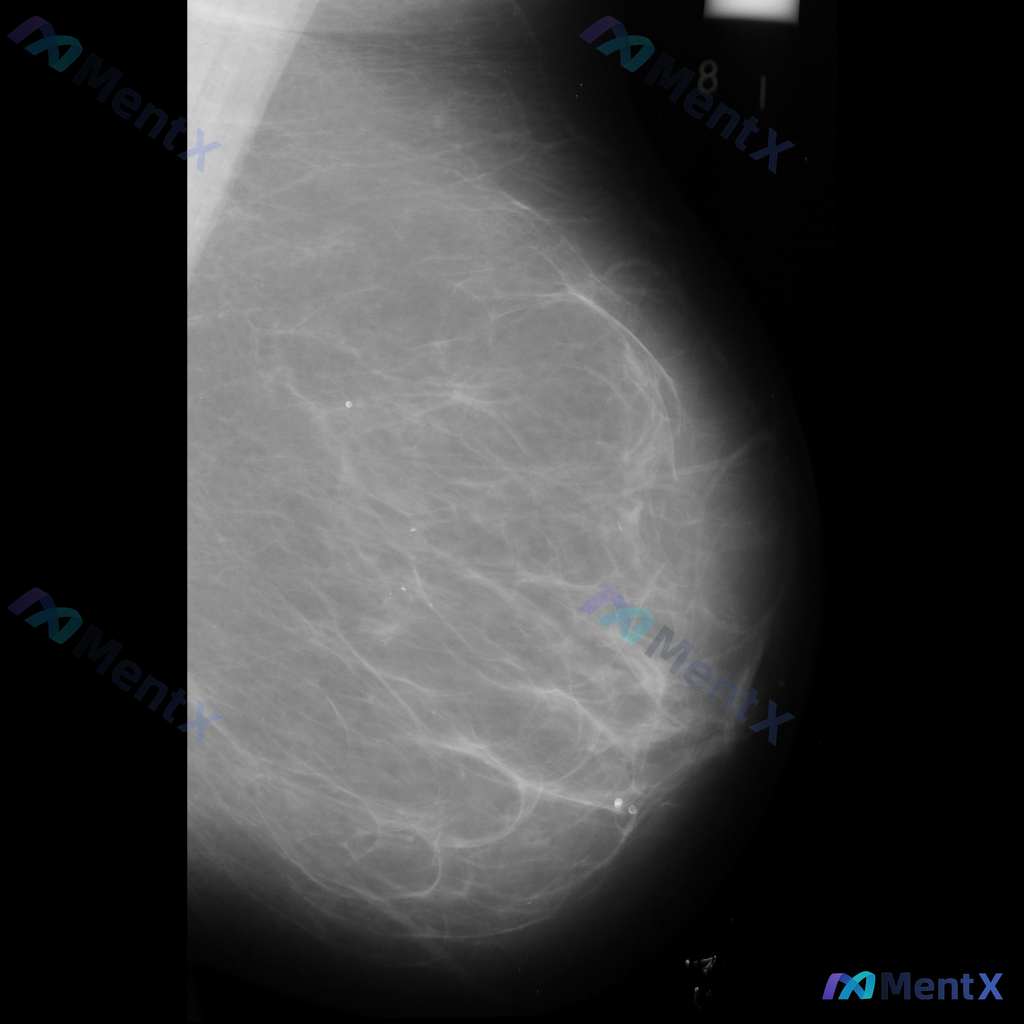

整理到一张乳腺钼靶影像资料,大家一起讨论下。 影像表现大概是这样: - 异常区域位于乳腺下象限偏外侧 - 可见一局限性致密影,形态大致呈卵圆形或不规则形 - 边缘部分清晰,局部可能模糊或有细微毛刺样改变 - 致密影密度高于周围脂肪组织,与纤维腺体组织密度相似或略高 - 周围乳腺小梁结构似有轻微的牵拉...